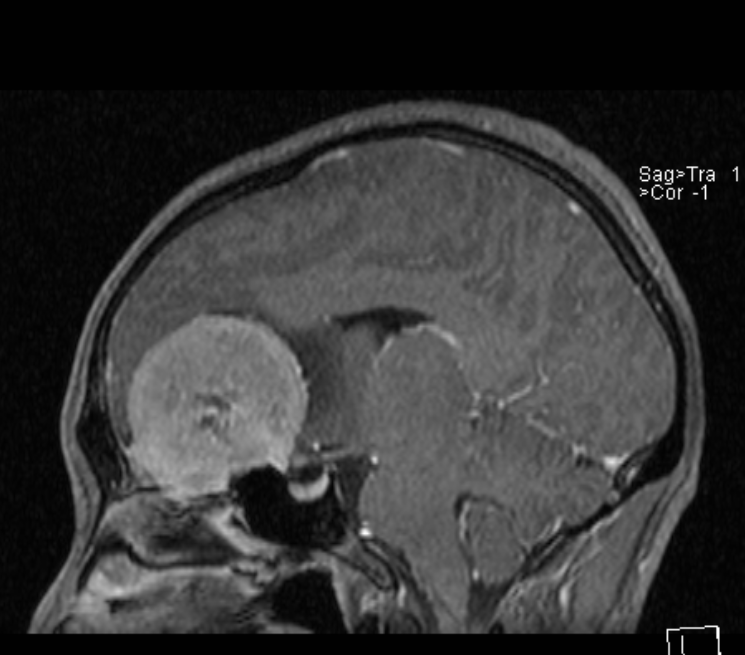

• 巨大脑肿瘤“鸠占鹊巢”,绵三医神经外科团队妙手除瘤

巨大脑肿瘤“鸠占鹊巢”,绵三医神经外科团队妙手除瘤 2023-11-03 作者:神经外科/金彪